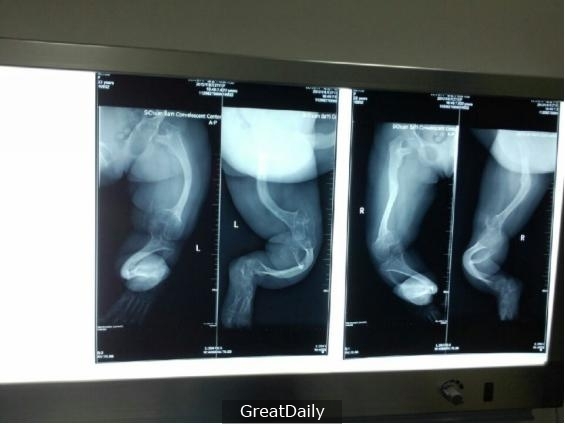

Vợ chồng cô nhanh chóng đưa con đến bệnh viện để kiểm tra. Sau khi chụp X-quang, bác sĩ cho biết xương bàn chân con chị có vấn đề, nó bị uốn cong khá nghiêm trọng. Bác sĩ rất thắc mắc vì sao lại như thế nên đã gặng hỏi người mẹ.

| Qua kết quả chụp X-quang cho thấy xương bàn chân của bé có dấu hiệu bị cong. |

Lúc này chị mới thú nhận rằng để tiết kiệm tiền, chị đã mua loại giày… dành cho người lớn cho con nhỏ đi. Bác sĩ khẳng định đó là nguyên nhân dẫn đến bé gặp tình trạng trên.

Theo bác sĩ phân tích, khi trẻ đang ở độ tuổi học đi, ngoài việc học cách đi, dáng bộ và cử chỉ nó cũng ảnh hưởng nhiều đến cách hình thành bàn chân của trẻ. Khi đi giày rộng, bàn chân trẻ bước đi sẽ không được vững chắc, bị xô dịch trong chiếc dép rộng lớn. Chính vì thế xuất hiện hiện tượng bàn chân bị cong.

Tuy nhiên, do trường hợp của con được phát hiện và cứu chữa kịp thời nên cuối cùng vẫn chưa xảy ra vấn đề quá lớn và có thể cứu chữa được. Nhưng, việc cha mẹ cho con đi giày dép quá rộng thực sự rất nguy hiểm đến sự hình thành xương bàn chân của con.